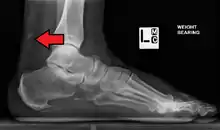

Magnetic resonance imaging may be useful to guide muscle biopsy and to investigate involvement of internal organs;[14] X-ray may be used to investigate joint involvement and calcifications.[15]